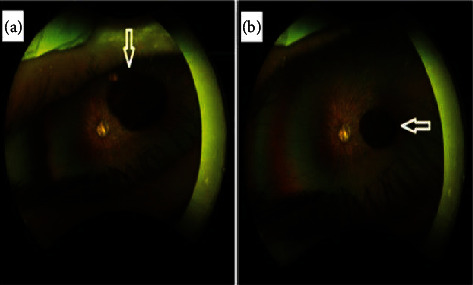

Vitreous cysts represent uncommon ophthalmological conditions. Most patients are asymptomatic, but a minority may experience symptoms such as floaters or blurred vision. Here, we report the case of a 2-year-old girl who was incidentally found to have a vitreous cyst in her left eye during a routine outpatient clinic visit. The cyst was observed to move with eye movements, was pigmented, lobulated, and measured 3 mm in diameter. Our patient exhibited several systemic manifestations. We recommended regular follow-up through clinical examinations and monitoring of the cyst using B-scan ultrasound.

Abstract Image